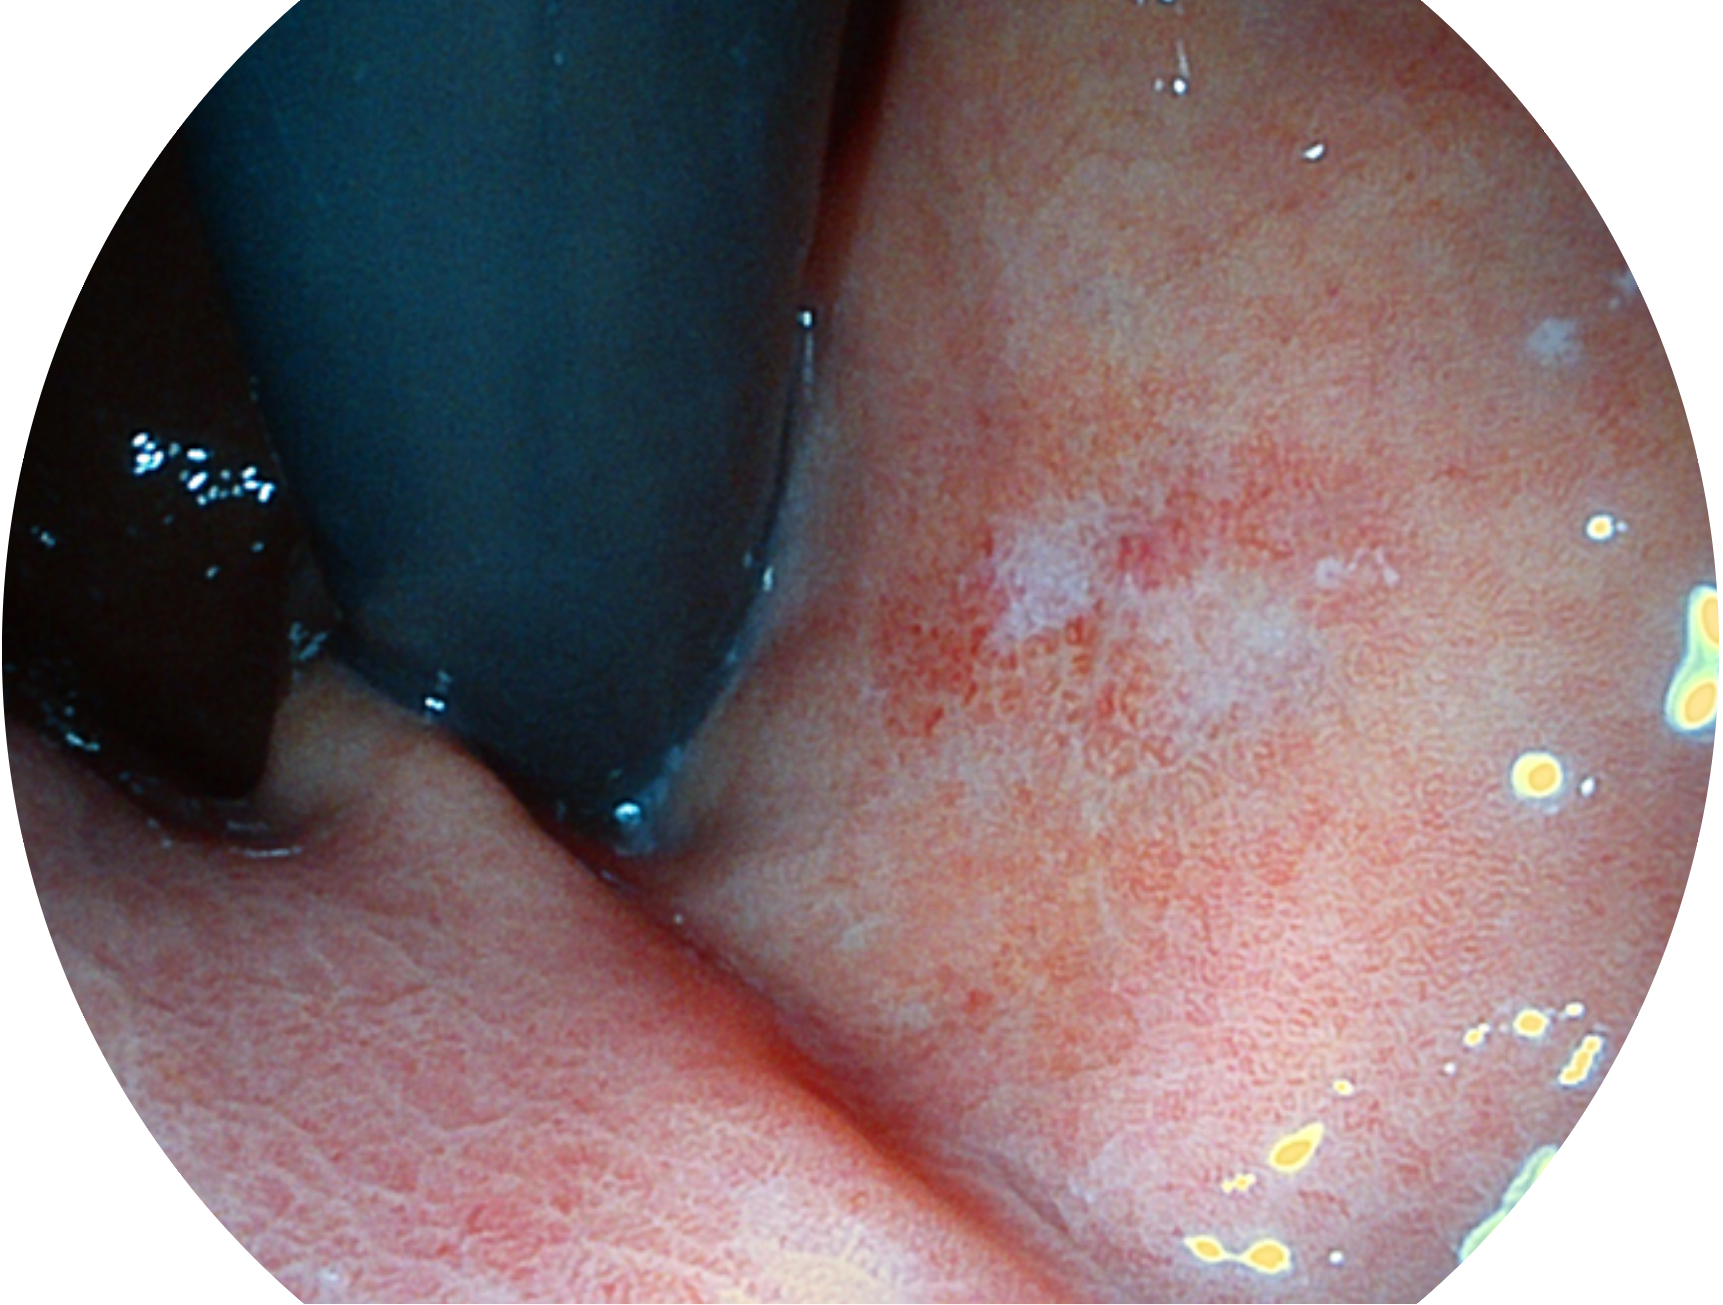

银河优越会新开发的内镜染色技术,主要是基于多波长LED 光源的开发,VLS-55Q 四波长LED 光源是由四个不同颜色的LED光按照相应照明模式所规定的特定发光比例进行合束后形成,合束后形成的照明光的光谱由红光、绿光、蓝光及蓝紫光这四个不同的波段范围构成。具有更高光谱自由度,通过光谱比例的控制,实现了聚谱成像技术,英文全称为“Spectral Focused Imaging, SFI”,缩写为“SFI”和光电复合染色成像技术,英文全称为“Versatile Intelligent Staining Technology, VIST”,缩写为“VIST”。